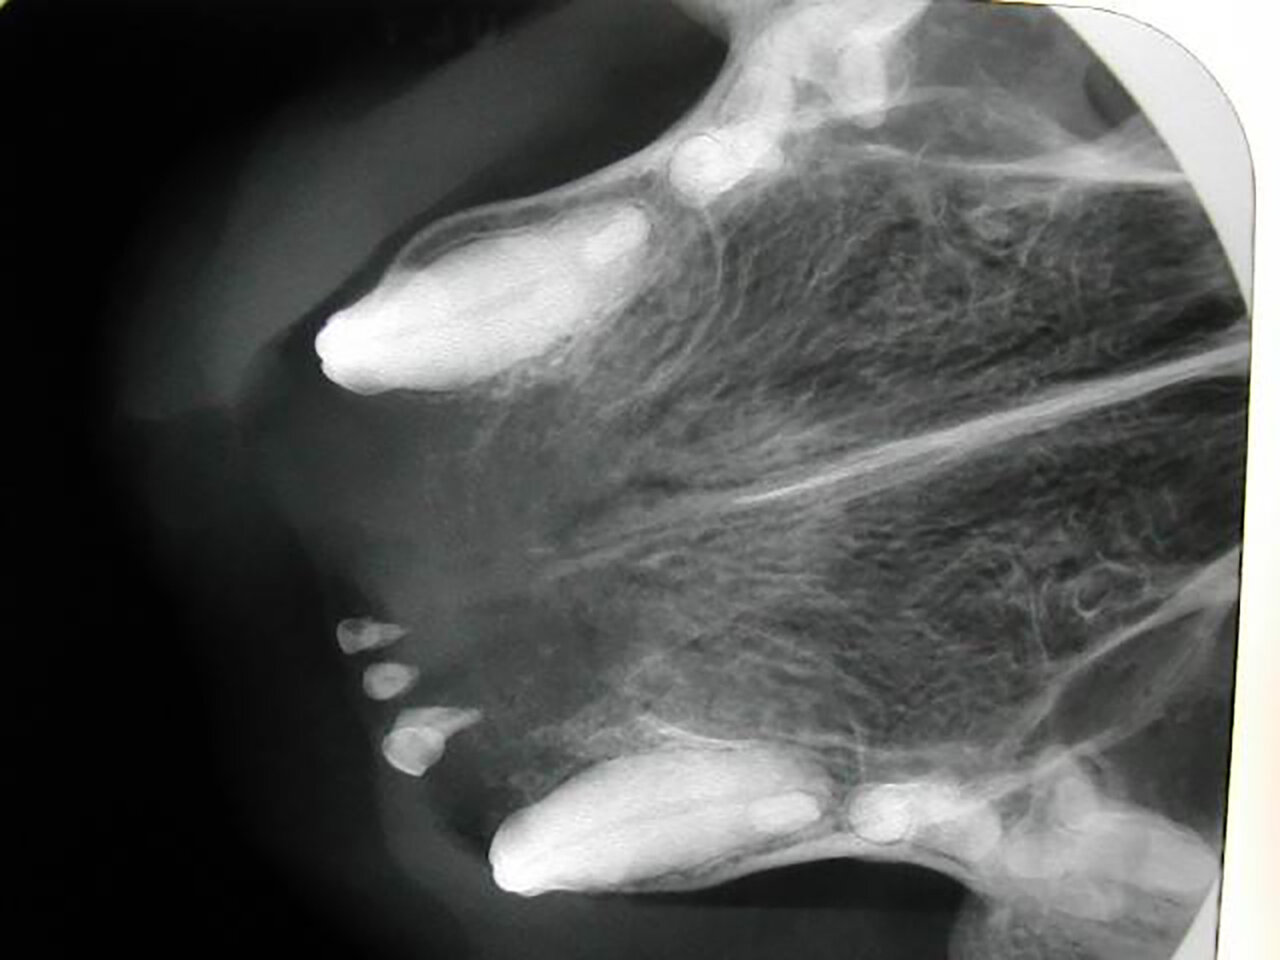

También puede ser debida a la pérdida dental (por EP, por ejemplo) o a fracturas de corona en las que quedan restos de estructuras dentales bajo la encía. Por tanto, dependiendo de ello, decidiremos el enfoque terapéutico que tomaremos en cada paciente con ausencia dental. (imágenes 14-17).

Aumento del número de dientes

La presencia de dientes supernumerarios también debe ser estudiada mediante la radiología intraoral. La causa principal es genética y la radiología nos permitirá valorar su naturaleza, si se trata de un diente definitivo o la falta de exfoliación de dientes deciduos (en caso de no tenerlo claro a la inspección visual). En este último caso, podremos valorar el estado de la raíz y su relación con el diente permanente, aspectos que debemos tener en cuenta a la hora de realizar su extracción (imágenes 18 y 19).

Las consecuencias pueden ser insignificantes en zonas de mínima intercuspidación, pero pueden ser causa de lesiones traumáticas o apiñamiento que disminuyan los mecanismos fisiológicos de autolimpieza.